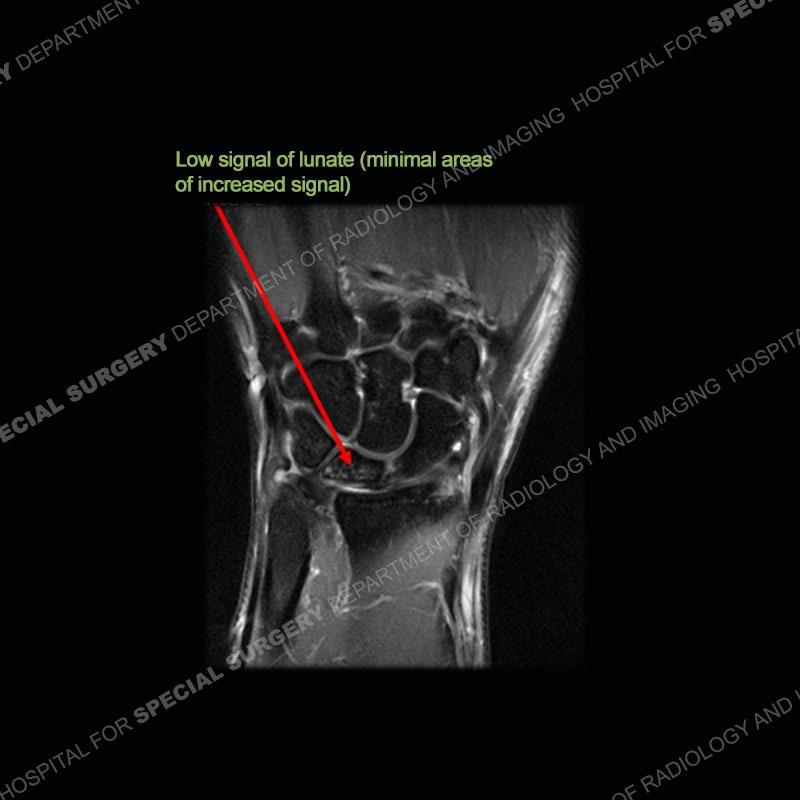

Both cases demonstrate similar findings to slightly less and more conspicuous degrees. The radiographs show sclerosis and fragmentation/collapse of the lunate. The CT images for case one just further clarify the architecture of the lunate. The MRI images show a slightly greater degree of variability but with overall persistent areas of low signal of the lunate on all pulse sequences and with a loss of the geometry of the lunate indicating collapse and fragmentation.

A well recognized but still poorly understood entity with necrosis and collapse representing the end stage of the pathology. The reasons for the necrosis are likely multifactorial and relate to the anatomy of the wrist inclusive of ulnar variance and the anatomy of the vasculature to the lunate. Other inflammatory, biological processes and overuse/trauma also likely play a role in the development of the necrosis. The disease manifests by sclerosis of the lunate followed by collapse and fragmentation. This is then followed by abnormal orientation of the scaphoid in a palmar flexed position and then adjacent arthritis. These latter processes were not the focus of this case presentation. The MRI will show areas of low signal on all pulse sequences indicating the areas of devitalized bone. The foci of slightly increased signal are in keeping with areas of maintained perfusion and highlight the variable architecture and findings of Kienbock’s. The fragmentation and collapse of the bone are seen well on both CT and MRI.